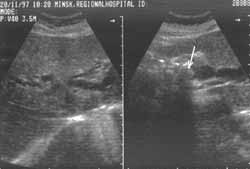

Ключевым признаком механической желтухи при УЗИ является расширение желчных протоков (Рис. 1), как внепеченочных так и внутрипеченочных. В норме внутрипеченочные желчные протоки, за исключением долевых, осмотреть которые возможно лишь в 50% случаев, при УЗИ не видны. Степень расширения желчных протоков при механической желтухе зависит от причин нарушения оттока желчи и в большей степени от продолжительности обструкции. Дилятацию внутрипеченочных протоков возможно выявить на 3-5 день после обструкции. Расширение протоков последовательно распространяется от места закупорки снизу вверх. Внутрипеченочные расширенные протоки при этом имеют вид мешотчатых или трубчатых структур и в отличие от ветвей воротной вены сохраняют значительную степень расширения и прослеживаются практически до периферии. Трудности в определении расширения внутрипеченочных протоков возникают в том случае, когда механическая желтуха возникает остро и по времени является непродолжительной, в случае преходящего холестаза при вентильных камнях, при мелких конкрементах холедоха, которые вызывают кратковременное нарушение проходимости.

Увеличить

Рис. 1. Расширены внутрипеченочные желчные протоки и холедох (22 мм). В желчном пузыре множественные конкременты (не показано).